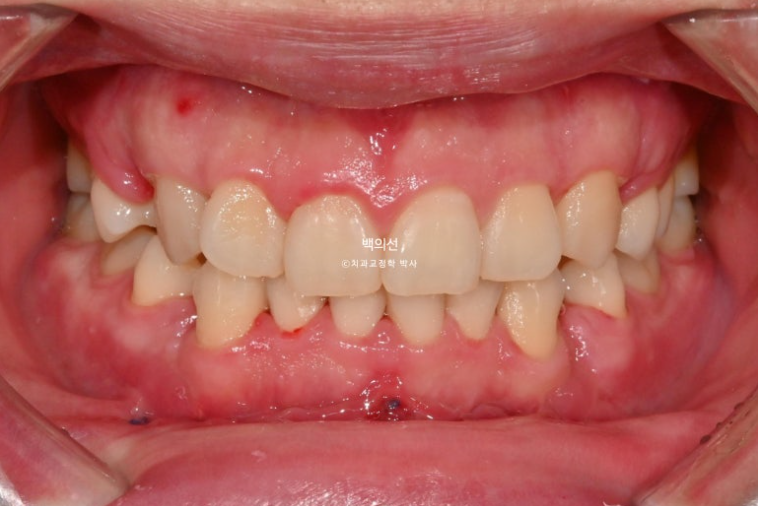

24년 10월, 돌출입 수술 한달 후 내원한 환자분 입니다.

24.10

돌출입 수술을 하면 수술 테크닉적으로 작은어금니가 있던 공간이 약 2mm 이상이 남게 됩니다.

송곳니 뒤쪽에 2mm 의 공간이 각각 남았습니다.

이렇게 애매하게 남은 공간을 앞니 배열을 위한 공간으로 사용하는 것이 돌출입 수술교정의 핵심입니다.